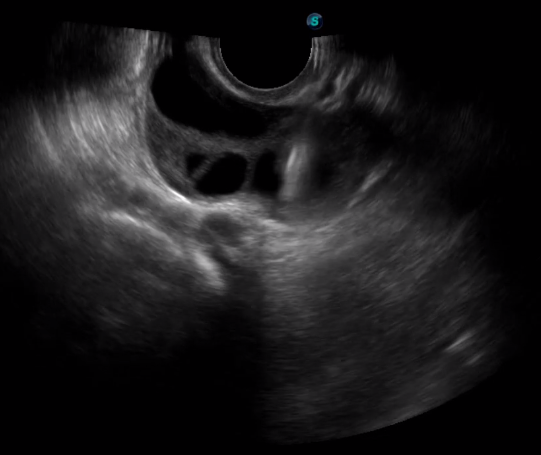

多數(shù)的生殖科醫(yī)生對(duì)于受精卵的植入采用憑經(jīng)驗(yàn)操作或是使用傳統(tǒng)腔內(nèi)探頭引導(dǎo),同樣存在手術(shù)空間小、受精卵放置位置不確定等風(fēng)險(xiǎn)。專業(yè)的宮腔專用探頭,配合專用的窺器使用,為醫(yī)生提供最大的手術(shù)視野。

胎移植臨床圖